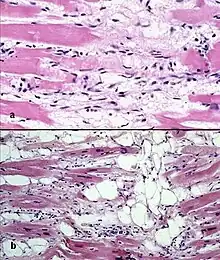

Il existe deux lésions pathologiques dans la dysplasie ventriculaire droite arythmogène : l'infiltration adipeuse et l'infiltration fibro-adipeuse :

- l'infiltration adipeuse est confinée au ventricule droit. Elle implique une substitution partielle ou quasi complète du myocarde par du tissu adipeux, sans amincissement de la paroi. Le ventricule gauche et le septum inter-ventriculaire (paroi séparant les deux ventricules) sont généralement épargnés. Il n'y a pas d'infiltration inflammatoire. Une dégénérescence des myocytes est mise en évidence dans la moitié des cas ;

- l'infiltration fibro-adipeuse implique le remplacement des myocytes par du tissu fibro-adipeux. Il existe une infiltration inflammatoire (principalement de lymphocytes T). L'atrophie du myocarde est liée aux lésions et à l'apoptose. Ceci conduit à un amincissement de la paroi libre du ventricule droit.